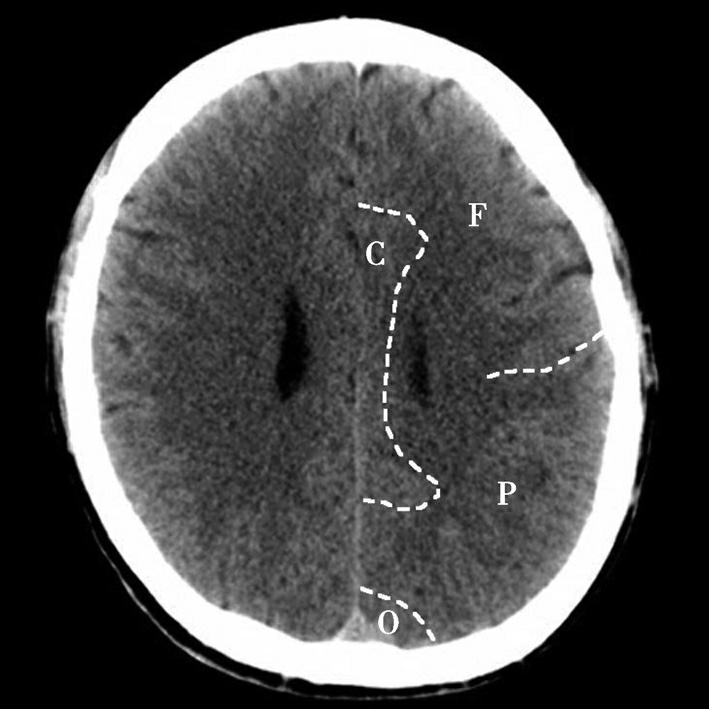

图1-2-36 脑叶划分示意图

F.额叶;O.枕叶;P.顶叶;C.扣带回

双侧侧脑室体部呈凹缘向外侧的镰刀状居中线两旁,以透明隔为界。尾状核体部紧贴侧脑室体部外侧壁,其外侧为双侧大脑半球白质,即放射冠,再外侧为岛盖。大脑半球内侧面被胼胝体分成前后两部,前部由前向后为额内侧回和扣带回,后部由前向后为扣带回、楔叶和舌回。大脑半球外侧面的脑回由前向后依次为额上回、额中回、额下回、中央前回、中央后回、缘上回、角回。顶枕沟位于半球内侧面后部,沟较深,呈水平走向,易于辨认。中央沟作为额叶与顶叶的分界线在此层面有时不易识别。